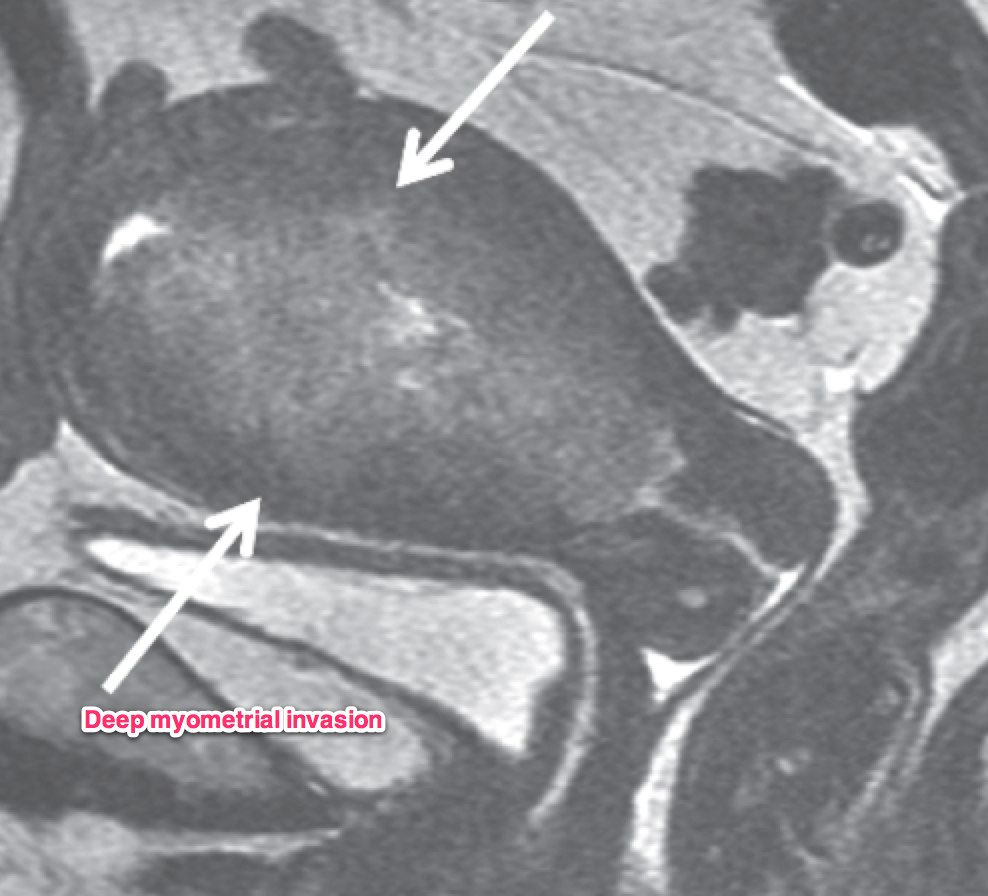

A transvaginal ultrasound should be obtained. In post-menopausal women, the expected endometrial thickness is < 4 mm. In pre-menopausal women, the thickness varies with the menstrual cycle. MRI is useful in identifying suspicious hyperplasia. If a thickened myometrium is visible on contrast enhanced CT, it is likely there is > 50% myometrial invasion. Cervical stromal invasion is seen on CT as an enlarged cervix, > 3 cm, heterogeneous stroma with low attenuation. Parametrial invasion is seen by loss of fat in the periureteral region, and fat plane near the pelvic sidewall.

Dynamic contrast enhanced MRI is optimal for MRI studies with accuracy of 85% or better. If there is a clear junctional zone between the tumor and the myometrium, the disease is most likely limited to the myometrium. MRI can also determine depth of cervical stromal invasion.